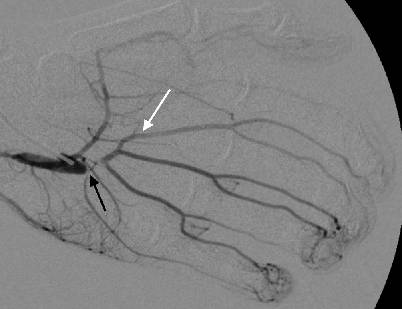

Am nachfolgenden Tag wurde das Pseudoaneurysma der A. ulnaris reseziert (Abb. 4) und ein Interponat mit der distalen V. basilica angelegt (Abb. 5). Die intraoperative Angiographiekontrolle über einen Seitenast des Veneninterponats zeigte eine gute Füllung der Arterien der ulnaren Langfinger (Abb. 6). Die postoperativen dopplersonographischen Verlaufskontrollen nach einer sowie vier Wochen zeigten neben einer guten Durchgängigkeit des Arcus palmaris superficialis auch eine gute Reperfusion der betroffenen Finger.

Abb. 6

Intraoperative Angiographie über einen Seitenast des Veneninterponats. Dargestellt ist ein Gefäßspasmus unmittelbar nach dem Interponat (schwarzer Pfeil), Kontrastierung des Arcus palmaris superficialis und der ulnaren Langfingerarterien (weißer Pfeil)